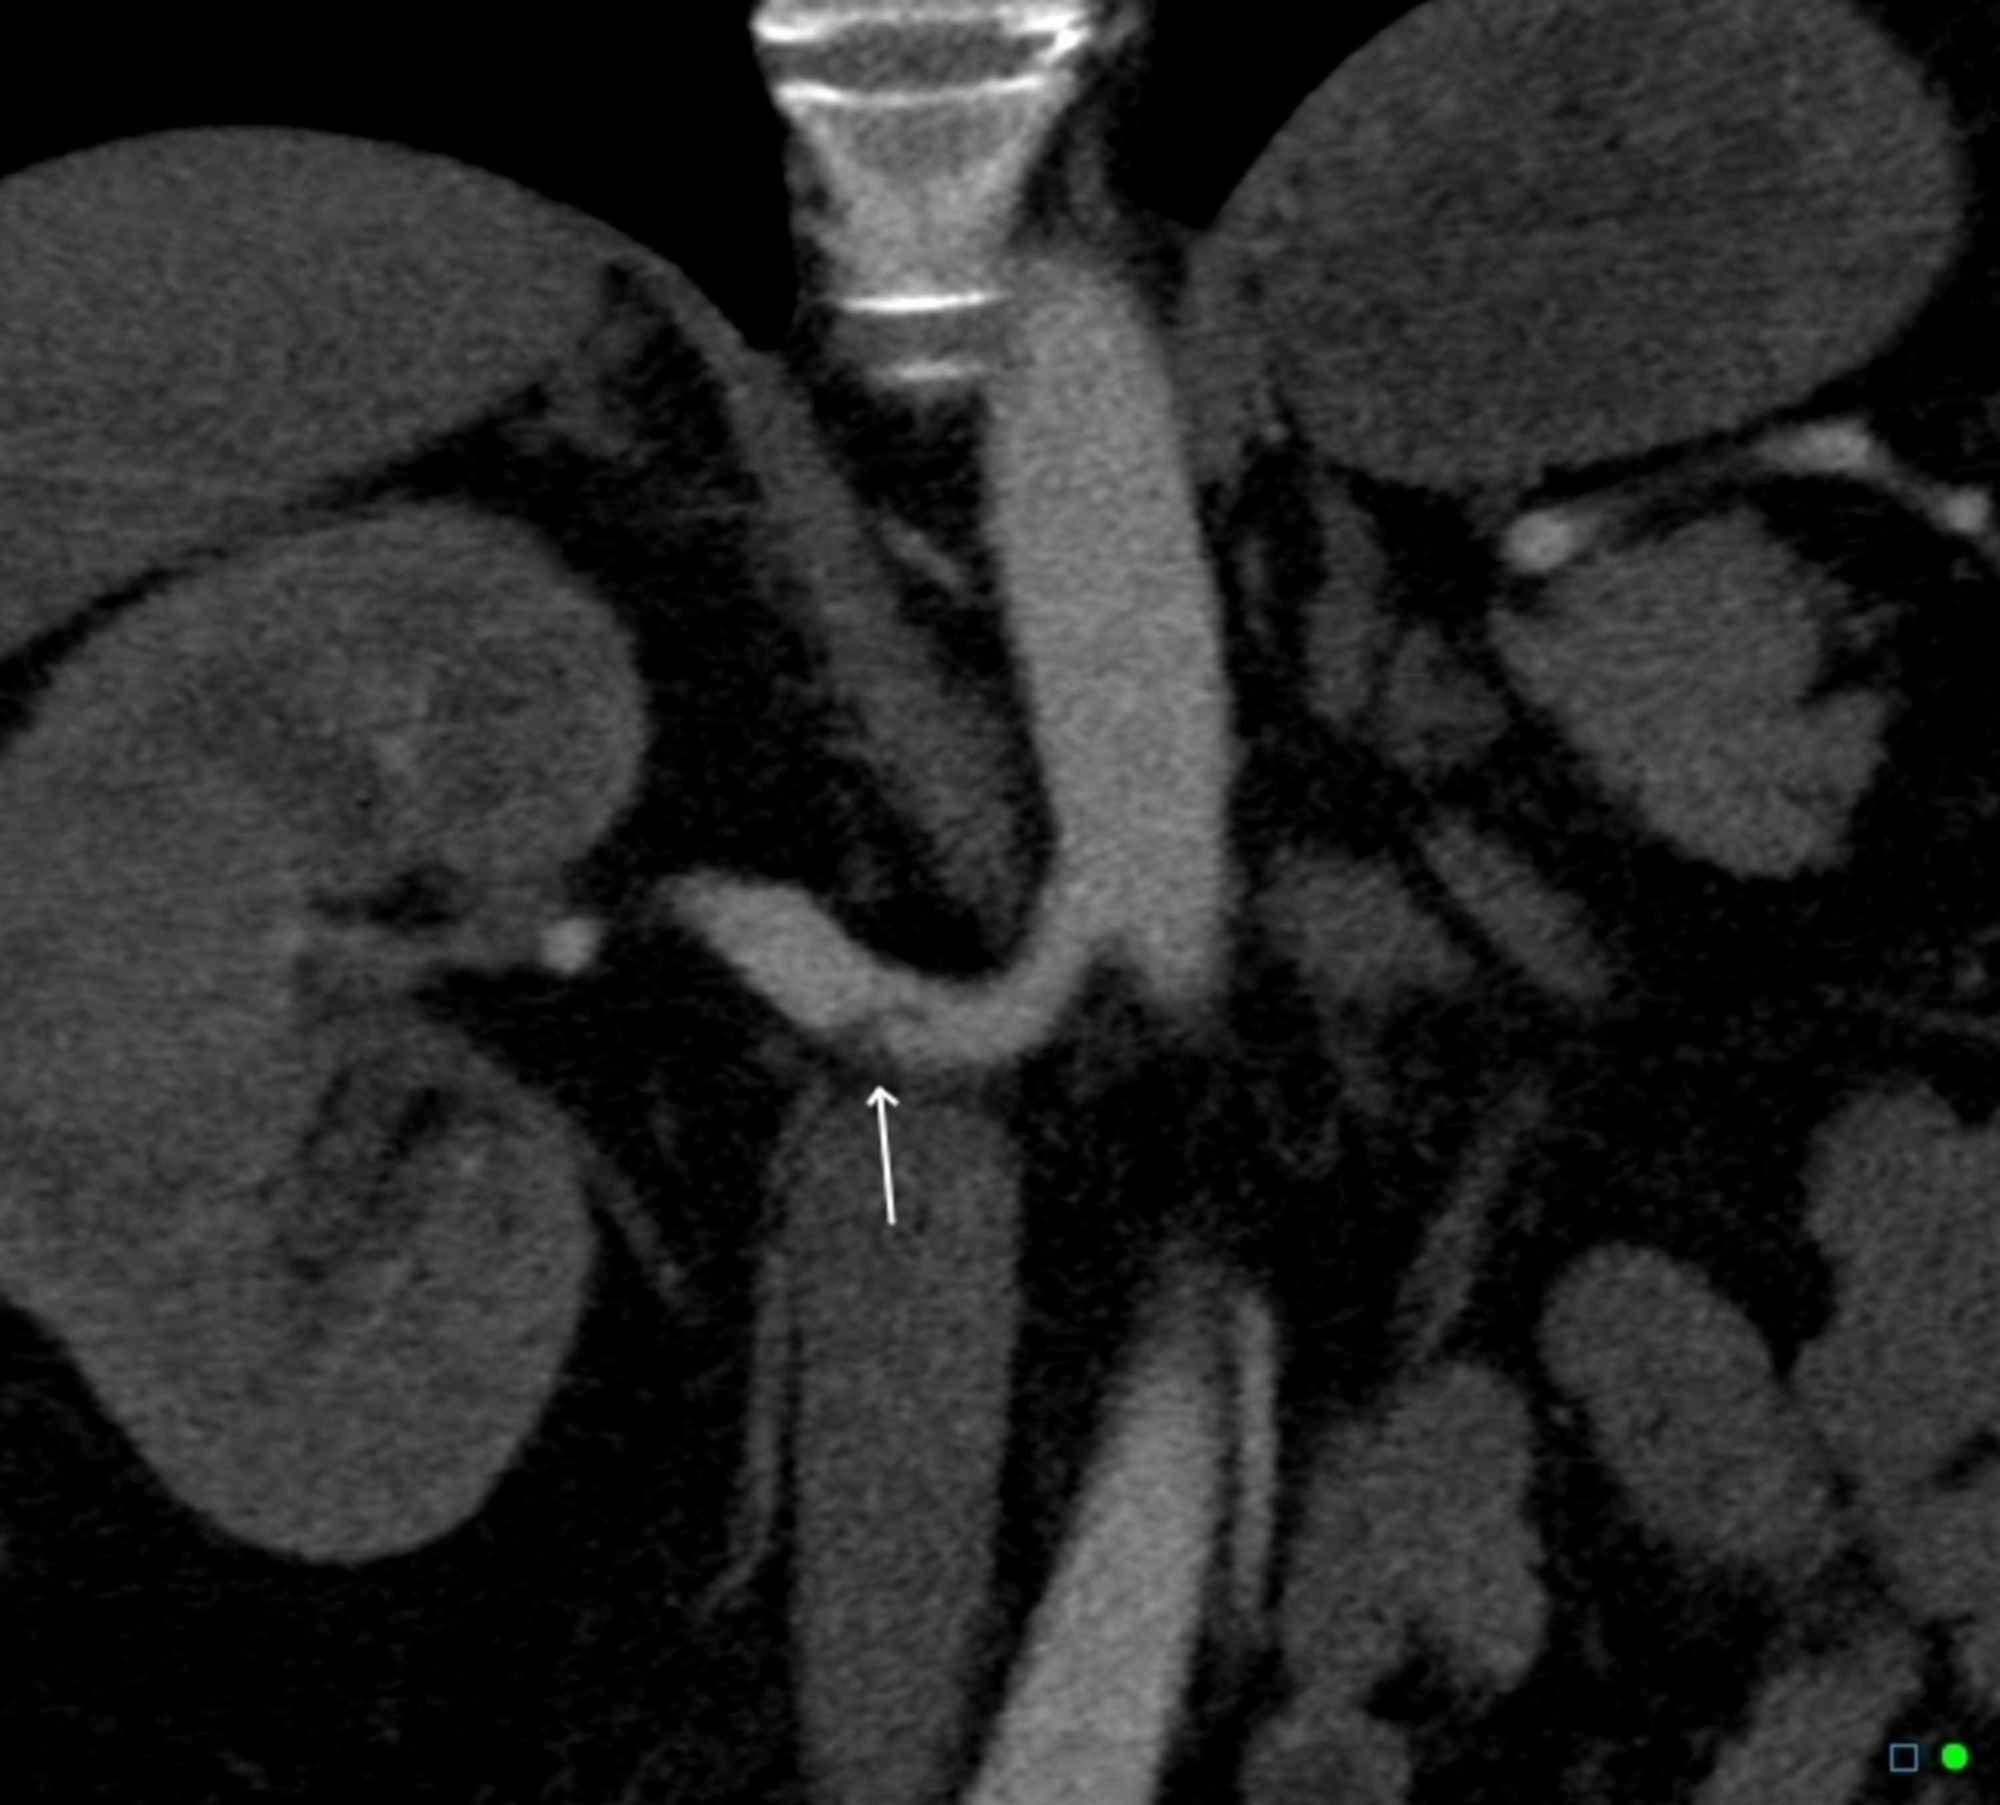

Figure 1 from Spontaneous renal artery dissection. Semantic Scholar

Figure 2 from Renal Artery Dissection in an Emergency Department Case Report Renal Artery Dissection Spontaneous renal artery dissection may occur spontaneously or secondary to local changes. In this case the renal infarction arose from a rare cause: These dissections can occur due. Spontaneous dissection of the renal artery. It is unusual for somatic type pain to actually. Renal artery (ra) dissections remain a rare and poorly understood disease process [1, 2]. Fourteen patients with. Case Report Renal Artery Dissection.